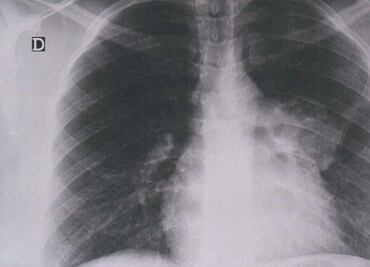

La enfermedad se presenta de igual manera tanto en hombres como mujeres

Un diagnóstico de cáncer de mama toma por sorpresa a todos, pero es más increíble cuando tal resultado lo recibe una mujer que no tiene ningún factor de riesgo, de acuerdo con su oncólogo.

Dependiendo de la etapa en la que se encuentre la enfermedad serán los gastos

El paciente de menor edad tiene 22 años y el mayor 49 años